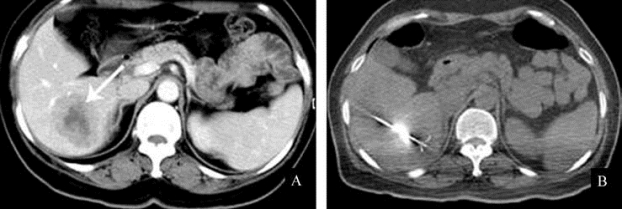

射频消融

(图21-26,图21-27);③生物免疫制剂或基因制剂等。